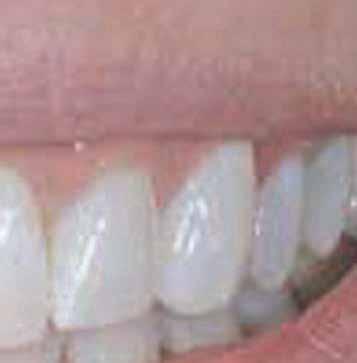

The inclusion criteria were patients within 20 to 40 years with unrestorable bilateral teeth with a harmonious gingival contour, having a thick

gingival phenotype, and at least 4 mm of bone apical to the root apex and 2mm labial plate of bone of the unrestorable tooth to be extracted and absence of any periapical radiolucency (Fig 1). 12 Any patient su ering from medical disorders interfering with osseointegration or soft tissue healing, active oral infections or periodontal disease, presence of dehiscence or fenestration defects related to the tooth to be extracted, poor oral hygiene, and heavy smokers was excluded from the study 13

Directly after immediate implant placement, a customized healing abutment was fabricated using Cervico kit. The selection was made intraorally using a special handle to place the indicator over the restorable area. (fig 6) Utilize the anatomical shape tab from the same group as per the anterior tooth missing. The anterior suitable stock healing abutment was directly screwed on the implant analog and was fixed at the corresponding well of the silicone mold, and the custom healing abutment was fabricated with nano‐hybrid flowable resin (3M™ Filtek™ Supreme Flowable Composite) (Fig 7,8). Minor selective grinding, finishing, and polishing were made when necessary to achieve a smooth, lustrous tissue contact surface, and screwed to the implant. 15 (Fig 9)